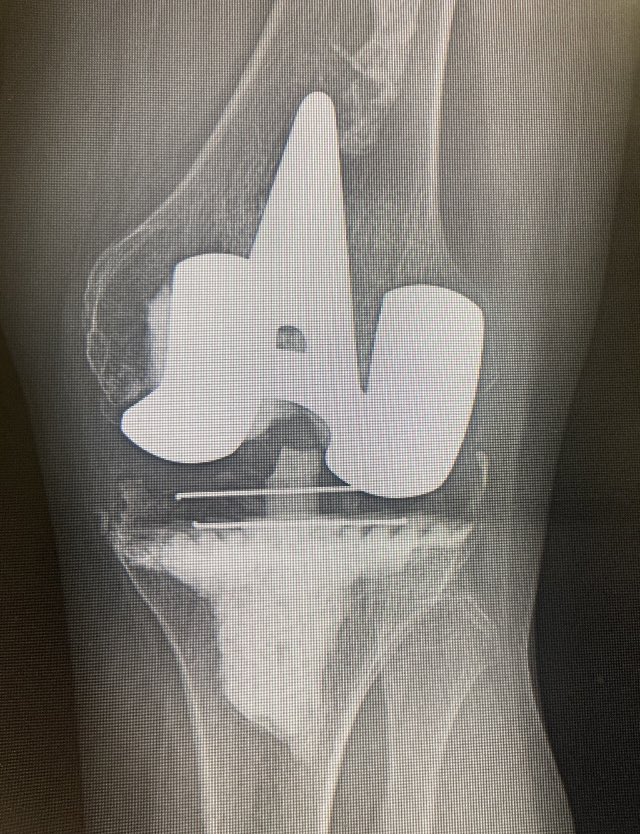

#OurWomanMentors arranca en Madrid el evento de #community dirigido al #liderazgo en traumatología. Coaching y magia para seguir creciendo. @AO_spain

Traumatology & https://t.co/mnYM2D4KUJ